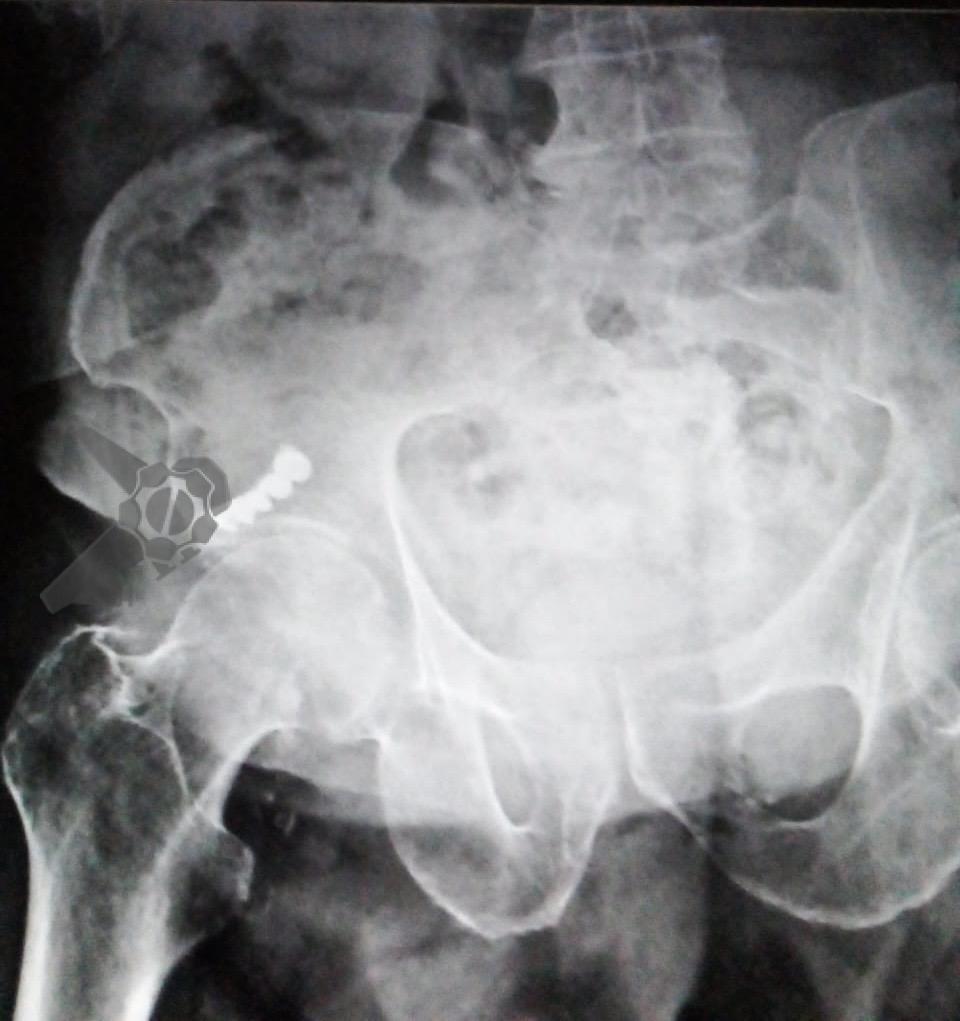

Masculino, 88 anos, aposentado, apresentando quadro demencial leve, assintomático, foi encaminhado ao serviço de endoscopia após a ingestão acidental de sua prótese dentária fixa. O incidente ocorreu há 15 dias, sem eliminação do objeto nas fezes desde então. Ele buscou atendimento na unidade de emergência de sua cidade, onde uma radiografia revelou a presença do objeto na topografia da fossa ilíaca direita (foto 1). Ao exame físico, não havia alterações relevantes com palpação do abdome inocente.

Após preparo colônico com manitol e a realização de uma nova radiografia, que não apontou qualquer mudança na posição inicial da prótese dentária desde a admissão, o paciente foi submetido a colonoscopia. Até a intubação cecal o corpo estranho não foi encontrado, com presença de doença diverticular no hemicólon esquerdo (foto 2 e 3).